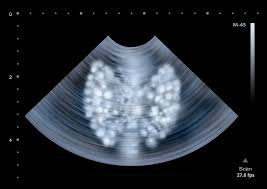

Doctoroncall is a platform where you can ask more about your health conditions. If the cancer cells look like they might have come from the larynx or hypopharynx, an endoscopic exam and biopsy of these areas will be needed. Ultrasounds cannot show if any change has been caused by cancer. The ultrasound also tells us if the ovaries have a normal surface texture and whether there are cysts within the ovaries. Two in three cases of thyroid cancer occur in people under age 55, and 75%.

The ultrasound also tells us if the ovaries have a normal surface texture and whether there are cysts within the ovaries. If the cancer cells look like they might have come from the larynx or hypopharynx, an endoscopic exam and biopsy of these areas will be needed. The outlook depends, to some extent, on where cancer starts. Ultrasounds are usually quick and most don't require special preparation. Your throat is a muscular tube that begins behind your nose and ends in your neck. The ultrasound also tells us if the ovaries have a normal surface texture and whether there are cysts within the ovaries. The cells are then looked at closely in the lab. What does ovarian cancer look like on ultrasound ? Ultrasounds are not useful for treatment monitoring. The survival rate in this type of cancer can be as high as 90 percent provided it is detected early in stage i itself. Hashimoto's thyroiditis is the most common cause of hypothyroidism in the us. What does throat cancer look like? Your voice box sits just below your throat and also is susceptible to throat cancer.